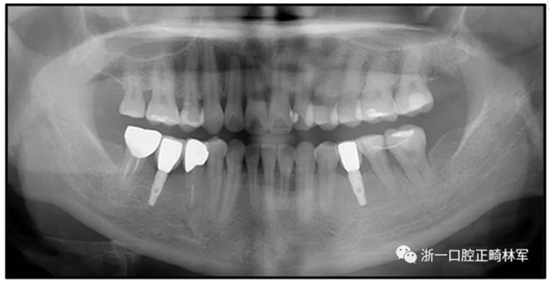

36歲;女性;尋求下頜左后方區(qū)域間隙管理的建議(圖1和圖2),通過治療獲得了良好的牙頜面效果(圖3和圖4)。她被診斷患有骨性I類和代償性牙性II類錯合畸形,并且上頜左側(cè)尖牙缺失(圖1和2)。大約七年前,由于不可修復(fù)的齲齒,拔除了下頜左側(cè)第一和第二磨牙(圖5)。37相鄰的第三磨牙向近中移動并傾斜入間隙,導致無牙頜間隙減小至約14 mm(圖2和圖5)。臨床和影像學評估顯示多發(fā)性齲損和在下頜右側(cè)567處有一不良的固定橋修復(fù)體(圖1和5)。此外,下頜左中切牙缺失,造成下頜中線向左側(cè)偏移約3 mm(圖1和圖2)?;颊咦栽V,她的右上第一前磨牙和左上尖牙在13歲時由其家庭牙醫(yī)拔除,因為它們被阻塞到頰側(cè)萌出(圖1)。上頜第二磨牙缺失(未知病因),并且相鄰的第三磨牙已經(jīng)轉(zhuǎn)移到第二磨牙間隙中。如補充材料所示,美國正畸學差異指數(shù)DI是28分。種植體部位(下頜左側(cè)和右側(cè)第一磨牙)由于復(fù)雜性得到額外4分(補充材料)。

圖5. 治療前的側(cè)位片(上圖)和全景(下圖)的X光片